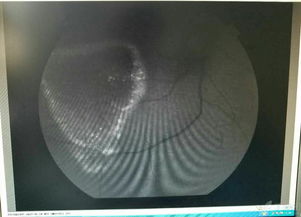

眼底熒光血管造影是將能產(chǎn)生熒光效應(yīng)的染料快速注入血管,同時應(yīng)用加有濾色片的眼底鏡或眼底照相機(jī)進(jìn)行觀察或照像的一種檢查法。

由于染料隨血流運(yùn)行時可動態(tài)地勾劃出血管的形態(tài),加上熒光現(xiàn)象,提高了血管的對比度和可見性,使一些細(xì)微的血管變化得以辨認(rèn);脈絡(luò)膜和視網(wǎng)膜的血供途徑和血管形態(tài)不同,造影時可使這兩層組織的病變得到鑒別;脈絡(luò)膜熒光可襯托出視網(wǎng)膜色素上皮的情況;血管壁、色素上皮和視網(wǎng)膜內(nèi)界膜等屏障的受損可使染料發(fā)生滲漏,這樣就可檢查到許多單用眼底鏡發(fā)現(xiàn)不了的情況,而且利用熒光眼底照相機(jī)連續(xù)拍照,使眼底檢查結(jié)果更客觀、準(zhǔn)確和動態(tài),從而為臨床診斷、預(yù)后評價、治療、療效觀察以及探討發(fā)病機(jī)理等提供有價值的依據(jù)。